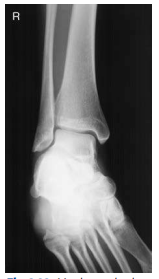

What ankle view is this?

AP